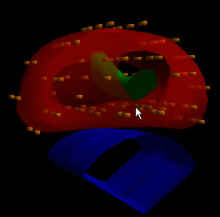

Photo: A radiation treatment plan for permanent prostate seed brachytherapy.

Photo: A three-dimensional rendering of seed positions for permanent prostate brachytherapy.

Both permanent and temporary prostate implants are available to our patients. Permanent implants (low dose rate, or LDR) involve the placement of many tiny radioactive seeds into the prostate gland under ultrasound. These implants are done in a single session. For temporary implants (high dose rate, or HDR), hollow catheters are placed into the prostate. A high-activity radioactive source is then fed under computer-control into each catheter and then removed. Temporary implants often can be done in one or two sessions. Both LDR and HDR implants can be done as the sole treatment for prostate cancer, or in some circumstances, in combination with external beam radiation.